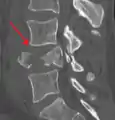

A burst fracture of L4 as seen on CT